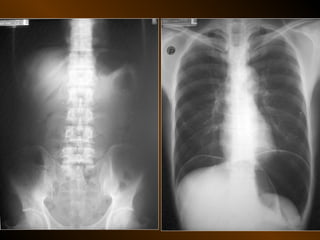

KHÍ TỰ DO

TRONG KHOANG PHÚC MẠC

NGUYÊN NHÂN

thủng tạng rỗng

nguồn gốc xuyên phúc mạc

nguồn gốc trong phúc mạc

10 – 15% thủng tạng rỗng → không thấy hơi tự do ổ bụng

KHÍ TỰ DO TRONGKHOANG PHÚC MẠC NGUYÊN NHÂN thủng tạng rỗng nguồn gốc xuyên phúc mạc nguồn gốc trong phúc mạc 10 – 15% thủng tạng rỗng → không thấy hơi tự do ổ bụng